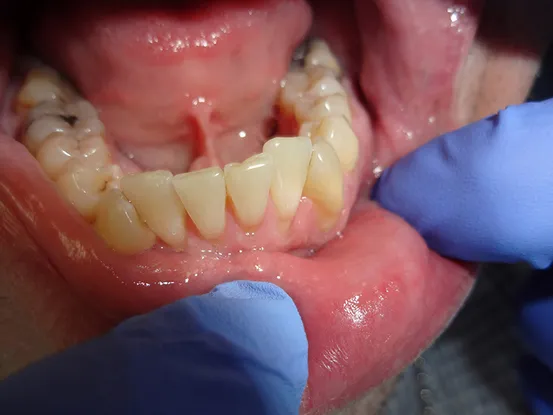

Case 7

38 year old female with extensive cervical caries from a high sugar diet and poor oral hygiene. 12 units of porcelain crowns and composite fillings to restore form and function followed by frequent recall visits